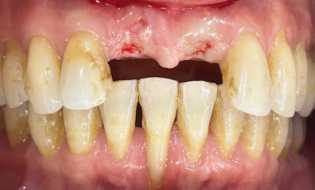

2nd surgery:

After

Figures 10 & 11

Figures 10 and 11 are a couple more cases which show our single incisor restorations which are notoriously difficult to get aesthetically right.